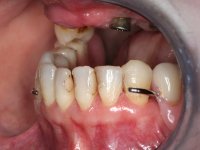

Paciente do sexo feminino, com 52 anos, não fumadora e portadora de uma prótese parcial removível acrílica superior e inferior. No maxilar superior estavam presentes os dentes 1.6/1.5/1.3 e 2.7. O canino apresentava-se com extração indicada. No maxilar inferior estavam presentes os caninos e os incisivos. As próteses removíveis utilizadas não estavam em boas condições. A paciente apresentava uma falta de apoio significativa do lábio superior mas as zonas edentulas do maxilar superior eram compatíveis com a colocação de implantes.

Inicialmente foram confecionadas duas novas próteses removíveis. O dente 1.3 foi extraído quando da colocação das próteses. Feito o estudo imagiológico necessário, foram colocados 4 implantes no maxilar superior. Após 3 meses de osteointegração foi feita a impressão para a confeção de ceras de articulação montadas em placa base aparafusadas aos implantes. Estas ceras foram utilizadas na recolha das relações inter-maxilares e na tentativa de proporcionar apoio ao lábio superior. Foi feita a prova de dentes com estes montados em placas base aparafusadas permitindo uma avaliação estética dinâmica muito interessante. Sendo validada esteticamente pela paciente, esta prova deu origem a uma muralha de silicone que orientou laboratorialmente a confeção da infraestrutura metálica. A infraestrutura metálica com os dentes montados em cera foi provada em boca, permitindo simultaneamente verificar a sua adaptação bem como a estética final. O trabalho final foi colocado em boca sendo acompanhado de instruções rigorosas de técnicas de higiene oral bem como da informação da necessidade de consultas de controlo periódicas.